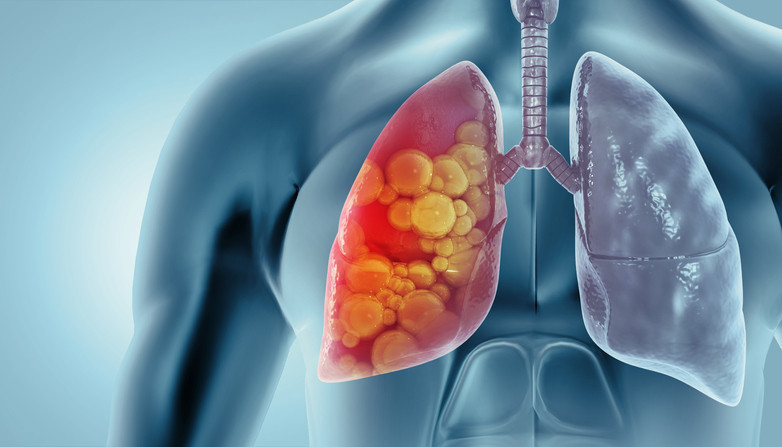

Pnömotaraks, KOAH, astım ve akciğer enfeksiyonları gibi hastalıkların yanı sıra göğüs bölgesine gelen darbe veya yaralanma sonucu gelişebiliyor. Yüksek basınç değişikliklerine maruz kalmak ve akciğer biyopsisi gibi yapılan bazı cerrahi girişimler de akciğerin sönmesine neden olabiliyor.

Akciğer hastalığı olanlar: Mevcut KOAH, amfizem ve akciğer fibrozisi gibi akciğer hastalığı olanlar da risk altında. Bu hastalıklarda akciğer “rezervi” zaten sınırlı olduğundan pnömotoraks hem daha kolay gelişebiliyor hem de daha ağır seyrediyor.